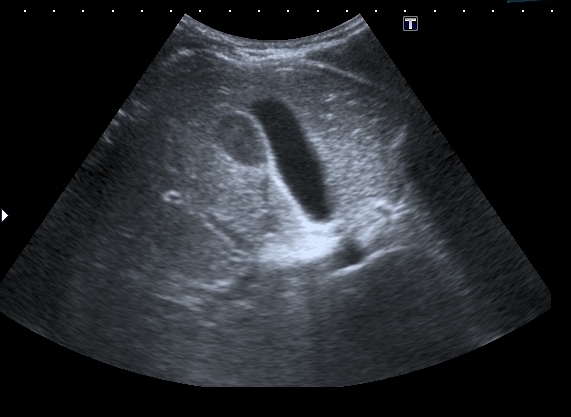

На УЗИ рядом с желчным пузырём определяется овоидное образование солидной струкутры с чёткими контурами.

При ЦДК кровоток в образовании не регистрировался, свободной жидкости в брюшной полости не было.